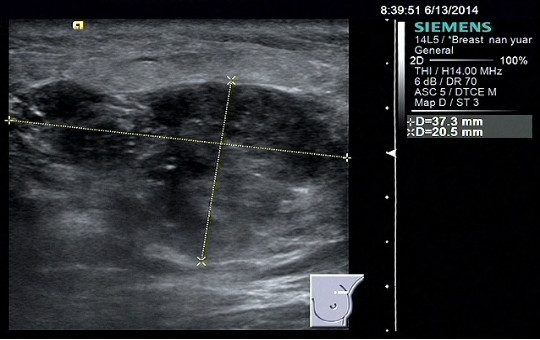

乳腺彩超:左乳外上象限2个肿物;大小分别 约12.9*10.8mm及25.8*20mm;边界不清,锯齿状,内部回声不均,可见血流信号,后方回声衰减;BIRADS分类:4C;左腋窝淋巴结肿大。